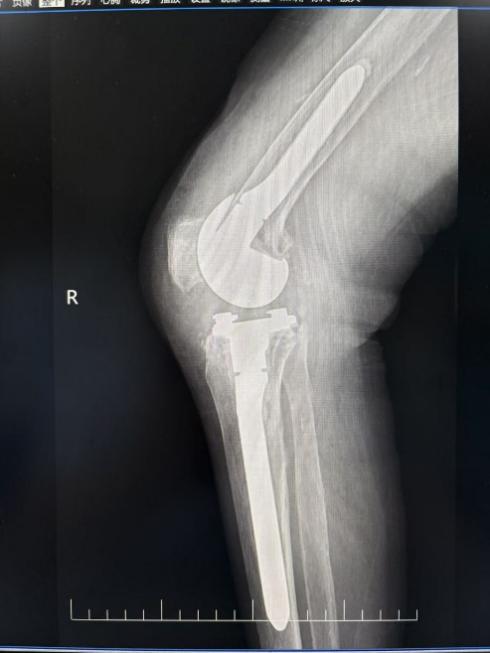

此次接受手术的欧阿姨,在2024年因右膝骨关节炎于外院进行人工膝关节置换术。然而,术后半年,她的膝关节出现红肿、疼痛且活动受限的症状,经诊断为 “右膝关节置换术后假体周围感染”。2024 年12月,欧阿姨转入湘南学院附属医院骨一科求诊。

治疗过程分多个阶段进行。首先是一期清创旷置术,医生们彻底清除感染坏死组织,植入抗生素骨水泥占位器,并进行关节腔内盥洗,有效控制局部感染。随后,进行关节液细菌培养,明确患者感染病菌为金黄色葡萄球菌,医疗团队以此为依据,迅速开展规范化抗感染治疗。联合静脉及局部用药,持续 4 个月动态监测炎症指标,确保感染完全得到控制。

2025年4月,当患者炎症指标稳定后,唐新文团队为其实施二期翻修手术。医务人员结合国际指南与本土化经验,采用“清创+抗生素骨水泥占位”策略,通过术后定期关节腔灌洗及血清学监测,极大地降低了感染复发风险,实现感染完全清除。针对长期感染导致的骨量丢失问题,唐新文团队创新采用3D打印定制垫块联合自体骨移植技术,精准恢复关节力线及生物力学功能。考虑到患者多次手术后的心理压力,刘红粘医生耐心安抚,帮助患者逐步建立治疗信心。术后,刘红粘医生联合康复科制定渐进式功能锻炼计划,结合疼痛管理及营养支持,患者术后第 3天就能借助助行器下地活动,实现快速康复管理。

如今,术后复查结果令人欣喜。患者关节活动度恢复至 0°- 110°,疼痛评分(VAS)从术前的8分降至1分。患者激动地说:“之前膝盖反复红肿,连走路都成问题,没想到还能重新站起来!”